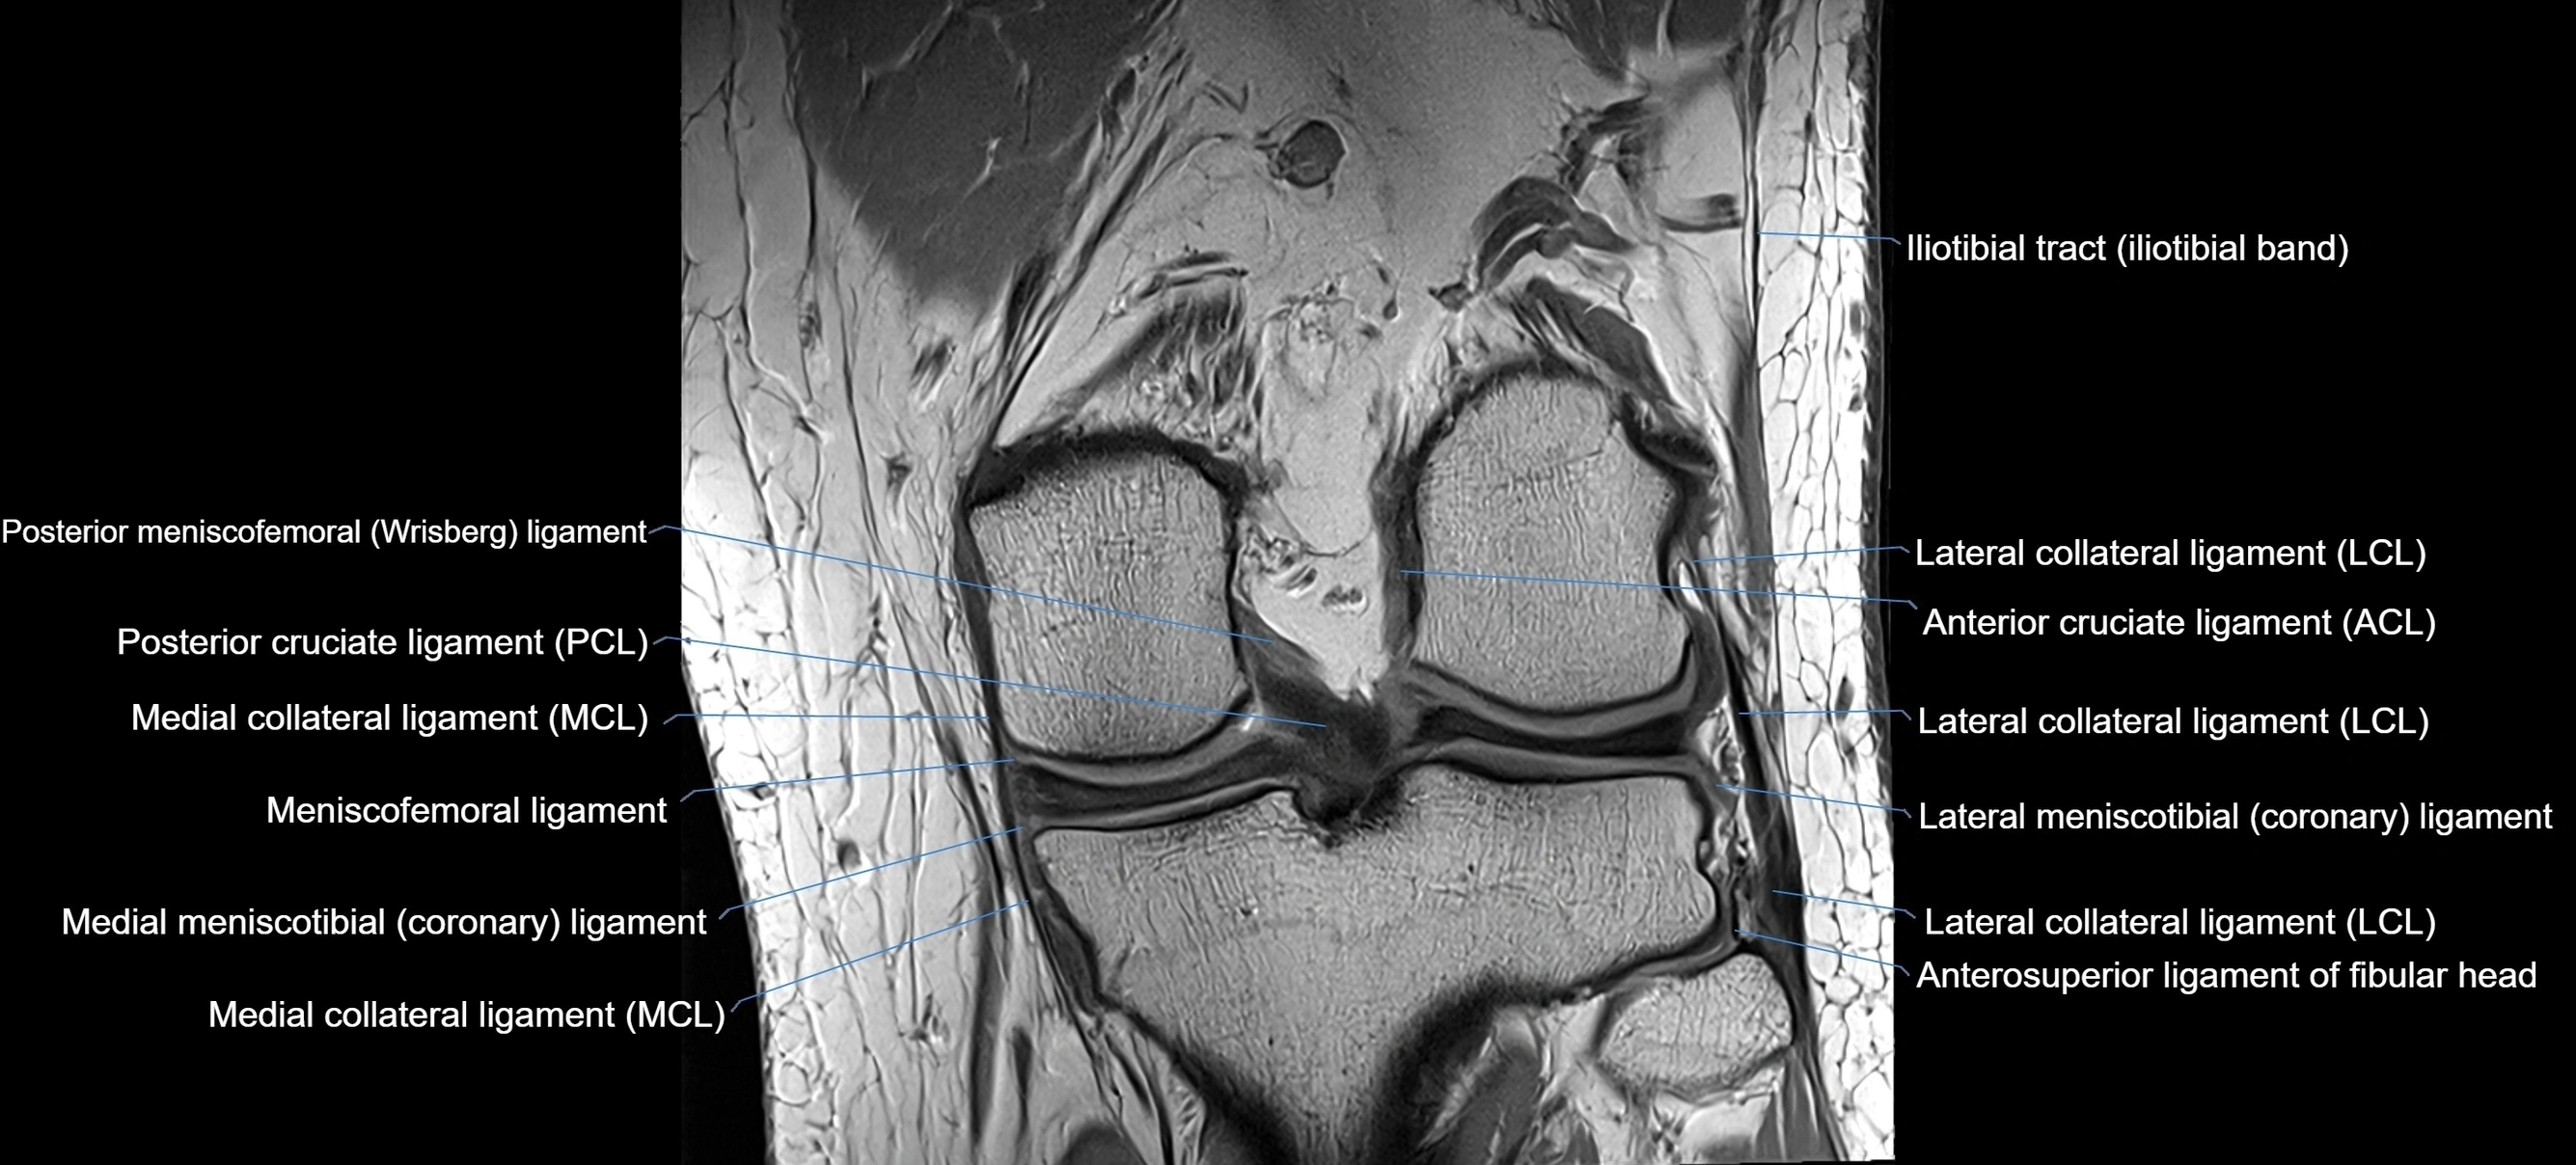

MRI images

image